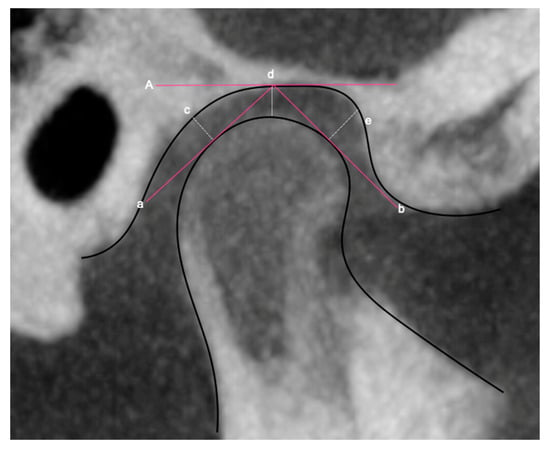

| Articular space | Posterior | Draw a tangent line to the posterior wall of the mandibular condyle. The most posterior-superior point of the condyle on the tangent line is located and from that point a perpendicular is traced to the posterior wall of the articular cavity. Data in mm. Figure 3c. |

| Middle | Draw a line from the uppermost point of the mandibular condyle to the deepest point of the glenoid fossa. Data in mm. Figure 3d. | |

| Anterior | Draw a tangent line from the most anterior part of the mandibular condyle. The most antero-superior point of the condyle on the tangent line is located and from that point a perpendicular is traced to the anterior wall of the articular cavity. Data in mm. Figure 3e. | |

| Condylar Position | Apply the equation: DC = (P − A/P + A) × 100%. DC (condylar displacement). P (posterior articular space). A (Anterior articular space). Method described by Pullinger and Hollender, modified by Pereira et al., 2007 [21,22]. | |